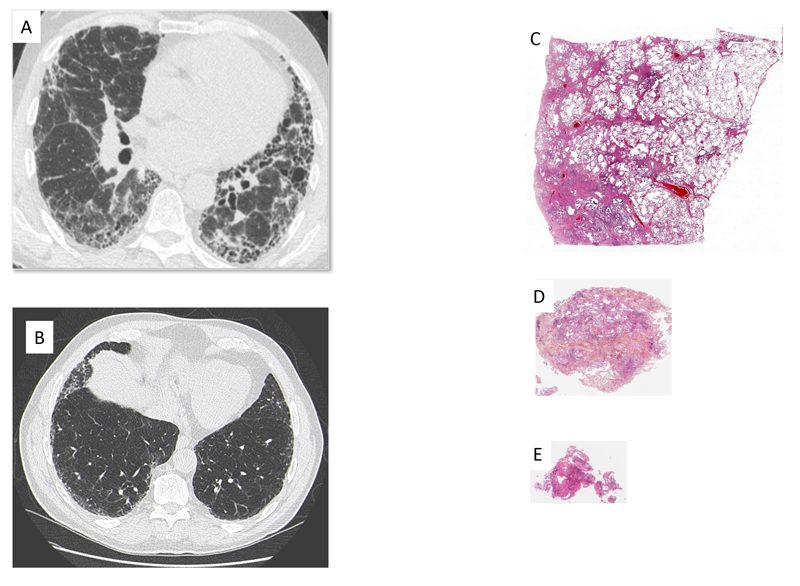

Figure 3 Scanner représentatif de (A) Pneumopathie interstitielle commune, (B) Pneumopathie interstitielle commune probable. Prélèvement histologique représentatif prélevé (A) par biopsie pulmonaire chirurgical, (B) par cryobiopsie, (C) par biopsie transbronchique.

L’identification de l’aspect de PIC peut être réalisée sur l’imagerie ou sur l’histologie (biopsie pulmonaire). Les progrès du scanner et les confrontations entre les données d’imagerie et anatomopathologiques ont permis de mieux caractériser l’atteinte interstitielle vue au scanner et de limiter le recours à une biopsie pulmonaire. Il a d’abord été démontré qu’un aspect de PIC au scanner, défini par la présence d’images en rayon de miel et une topographie sous-pleurale et basale des lésions, avait une valeur prédictive positive de plus de 95 % de PIC histologique, permettant ainsi de se passer d’une confirmation histologique. Il a ensuite été montré qu’un aspect de «PIC probable» au scanner, défini par la présence de bronchectasies par traction périphériques et de réticulations, de topographie prédominante sous-pleurale et basale, sans rayon de miel, permettait également, dans un contexte clinique évocateur de FPI, de prédire une PIC histologique et ainsi de poser un diagnostic de FPI sans recours à une confirmation histologique [2].

Malgré ces progrès radiologiques permettant de diminuer le recours à une biopsie chirurgicale et en l’attente de confirmation des résultats prometteurs des analyses automatisées des scanners thoraciques, il est encore parfois nécessaire d’obtenir une confirmation histologique de PIC.

Les progrès chirurgicaux et la meilleure sélection des patients ont permis de diminuer la morbi-mortalité de cet examen invasif. Parallèlement la technique de cryobiopsie a été développée. Il s’agit d’une technique endoscopique dans laquelle une cryosonde est introduite par le canal opérateur. Cette sonde permet de congeler les tissus avoisinants sur plusieurs millimètres en quelques secondes. Un morceau de poumon gelé de 5 mm d’arête au moins peut ainsi être obtenu et permet une analyse histologique représentative de parenchyme pulmonaire. Ainsi dans une étude prospective récente, dans 95 % des cas, si le degré de confiance dans le diagnostic était élevé, le diagnostic histologique proposé par cryobiopsie était concordant avec celui de la biopsie pulmonaire chirurgicale. En revanche, quand le degré de confiance était plus faible, la classification était modifiée pour 23 % des patients entre les 2 techniques[3]. De plus, d’autres techniques encore moins invasives sont en cours de développement, et une méthode basée sur l’analyse transcriptomique des biopsies transbronchiques pour le diagnostic de FPI est ainsi déjà approuvée aux États-Unis, bien que les données soient pour l’instant encore limitées[4].